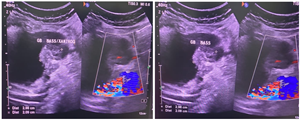

Background: Xanthogranulomatous Cholecystitis (XGC) is a benign inflammatory condition whose features often closely mimic Gallbladder Carcinoma (GBC). In GBC-endemic regions like Eastern India, this diagnostic uncertainty is intensified, frequently leading to unnecessary radical surgical intervention. This study aimed to characterize the clinical presentation, diagnostic limitations, and surgical burden of XGC in a high-risk cohort. Methods: This was a retrospective, single-center study of 48 patients with histopathologically confirmed pure XGC over a two-year period (Jan 2022–Dec 2023). Postoperative outcomes were rigorously assessed using the Clavien-Dindo classification. Results: The cohort showed a marked female predominance (62.5%) and mean age (53.8 years) consistent with local GBC demographics. Radiological non-specificity was profound: 91.7% of benign XGC cases exhibited mucosal gap/disruption, a feature conventionally associated with malignancy. This severe diagnostic uncertainty resulted in 37.5% of patients undergoing unnecessary extended resections, which translated to a high 20.8% major postoperative complication rate (Clavien-Dindo ≥IIIa). Conclusion: The high clinical and surgical burden of XGC demands an urgent institutional shift toward a definitive preoperative diagnosis, necessitating immediate review of imaging and frozen section standards. The essential next step is a prospective, multi-center study to develop and validate a Machine Learning (ML)-based predictive nomogram to ensure the diagnostic certainty required for safe, conservative XGC management.